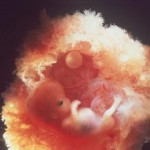

Voici à quoi ressemble le fœtus à la semaine 11 (cliquable):

L'enfant entier a maintenant la taille de la chaux. La longueur du corps est de 44 à 60 mm et le poids est d'environ 8 g.

Tous les organes et systèmes de l'enfant sont déjà formés. Ils sont dans un état différent. Par exemple, un petit cœur bat longtemps et complètement. Mais il n'y a pas encore de squelette, le tissu osseux reste au stade cartilagineux. Jusqu'à présent, seuls les globules rouges (globules rouges) sont contenus dans le sang et les globules blancs se forment plus tard. Mais les cordes vocales se sont presque développées, bien que le bébé n'en aura pas besoin bientôt.